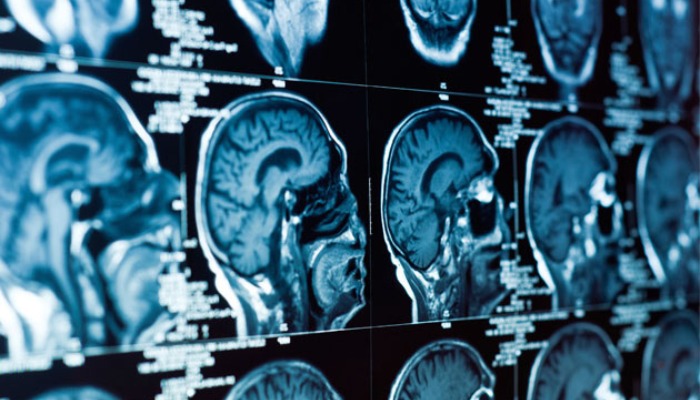

Brain surgery, also known as neurosurgery, involves the diagnosis and surgical treatment of conditions affecting the brain, skull, and surrounding structures. These procedures demand the highest level of precision, skill, and technology.